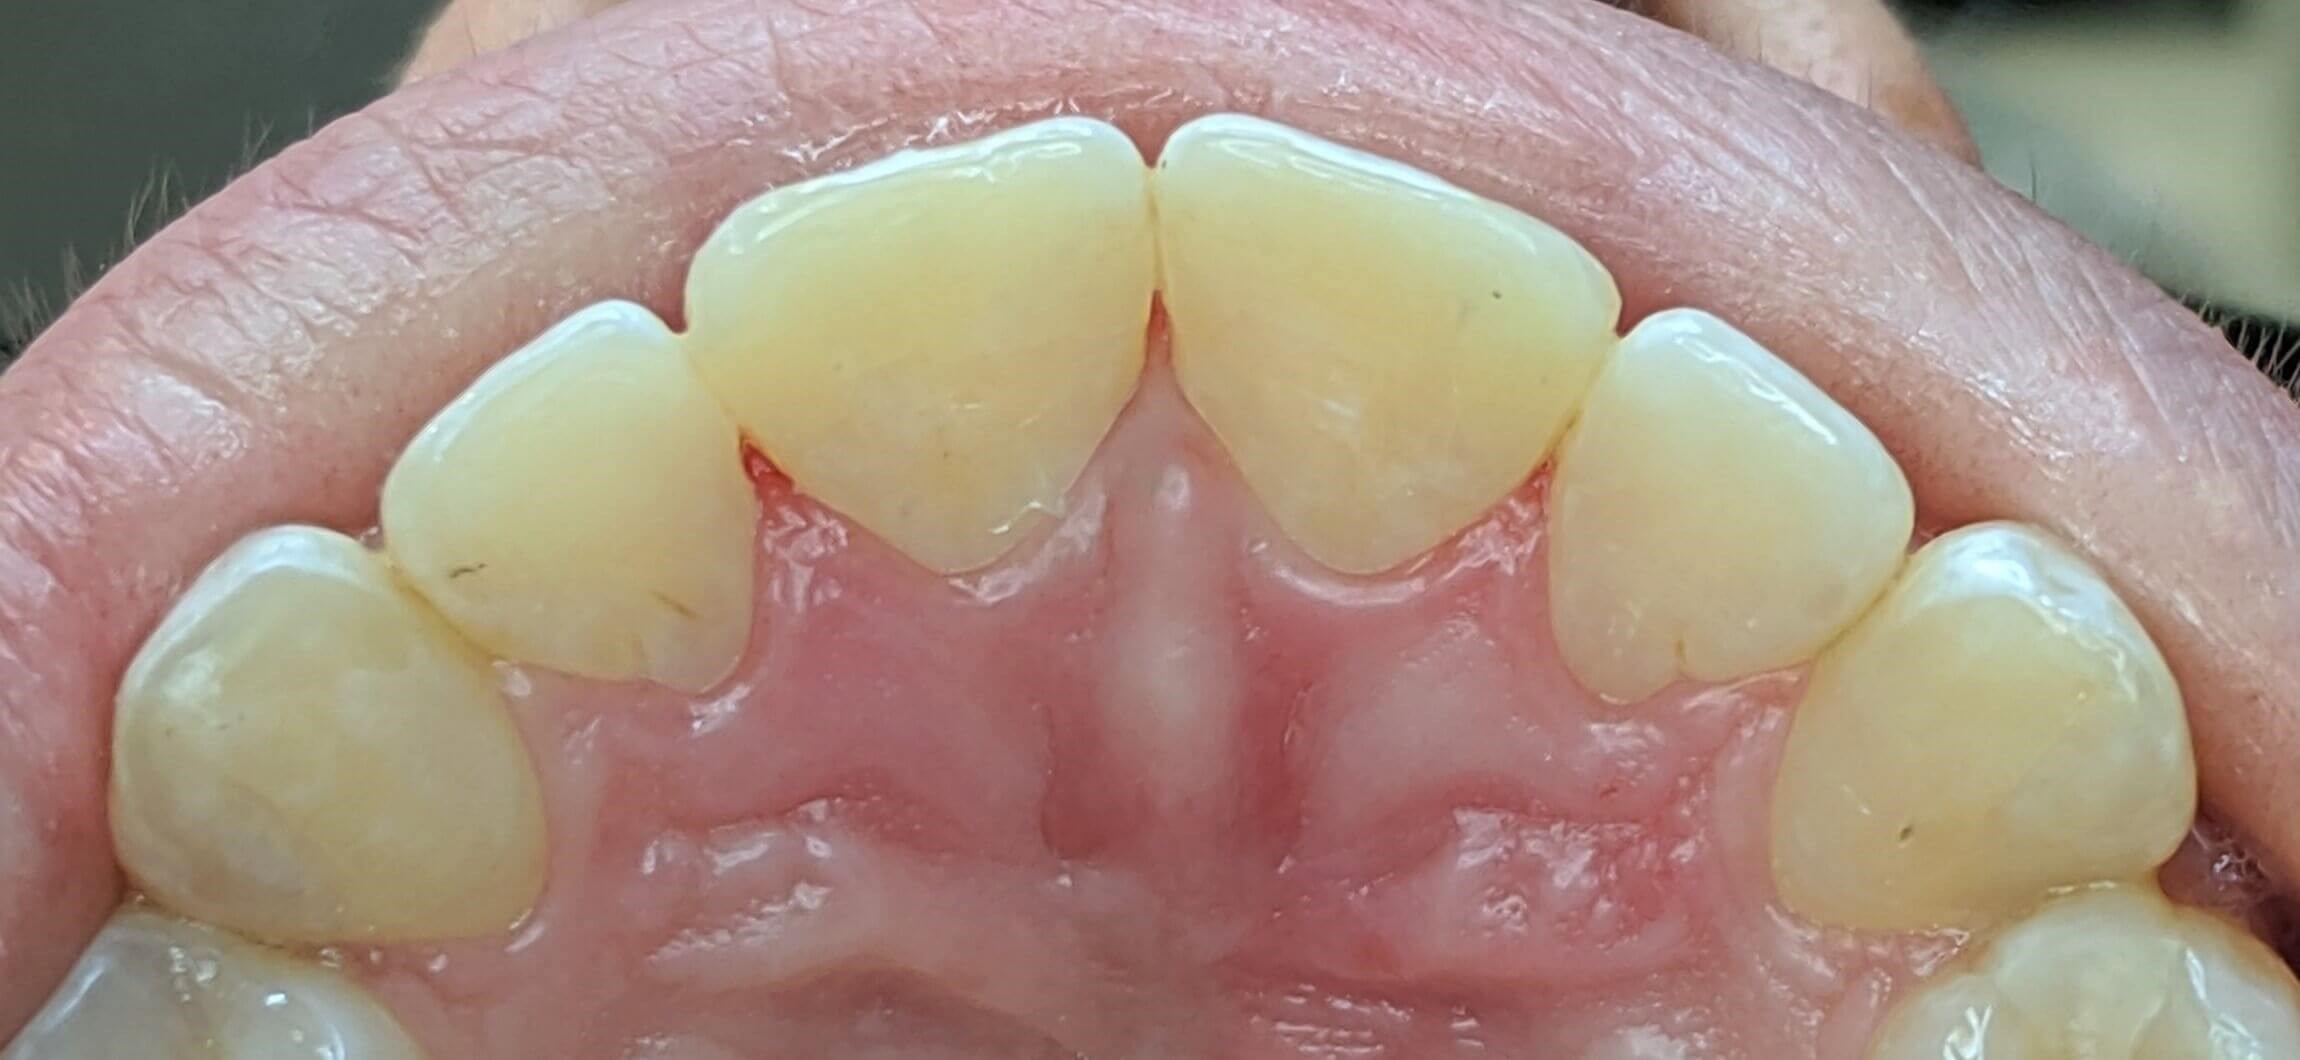

Tooth-colored fillings often fill in the decay in the enamel after it has been cleaned. Composite resin is a versatile material that can be used to treat other problems with your teeth, including cracks or enamel that has been worn down by teeth grinding (bruxism). Since the composite resin is colored to match your natural teeth, tooth-colored fillings can be used on both the front and back teeth for a seamless appearance. If you have metal fillings, talk to Dr. Kim or Dr. Chang about having them removed and replaced with tooth-colored fillings.

Getting a filling at Luminous Dental Studio is typically an easy process. The area surrounding the cavity will be numbed with a local anesthetic to minimize your discomfort. Other forms of sedation can be discussed if you have any fears or dental anxieties to help keep you at ease during the procedure. Once you are prepared, the decayed enamel is removed with a unique dental drill that Dr. Kim or Dr. Chang will select based on where the cavity is located in the tooth and the level of decay. After the enamel is removed and the tooth is cleaned, the cavity will be filled with the composite material and set with a special light. Dr. Kim or Dr. Chang will polish the filling so it feels comfortable and matches your natural teeth.

Yes, they do. The main benefit of tooth-colored fillings is the fact that they don't change the natural color of your tooth — so no one but you will know you have a filling.